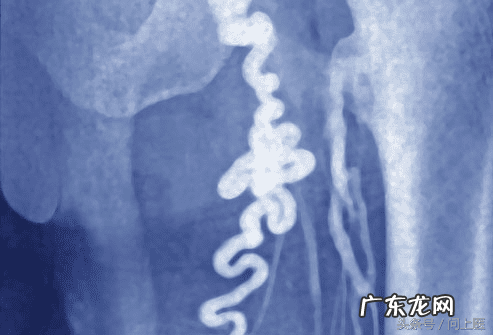

13/20 肾结石

文章插图

人体内盐和矿物质在肾内积聚形成结石是正常的生理现象 。大部分肾结石像沙子一样大,可通过尿道顺畅排出体外 。但也有的结石较大,个别的甚至跟高尔夫球一样,它们排出过程异常艰难,会引起剧烈的疼痛 。如果你的尿液变成粉红色或者血红色,那么就需要医生帮助排石 。如果情况并不严重,医生会嘱咐你多喝水,从而利用排尿过程将之排出 。另外,为了帮助你缓解疼痛,医生可能会给你开些止痛药 。